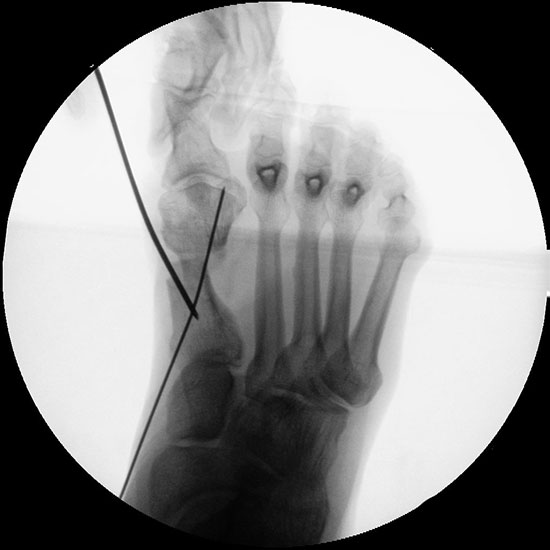

Abbildung 1

• Korrekturpotential größer als beim offenen Chevron, da die Gelenkkapsel als stabilisierendes Element erhalten bleibt und über eine trikortikale Osteosynthese mit zwei kanülierten Schrauben eine Verschiebung bis ca. 80% des Metatarsaledurchmessers möglich ist (Abb. 1).